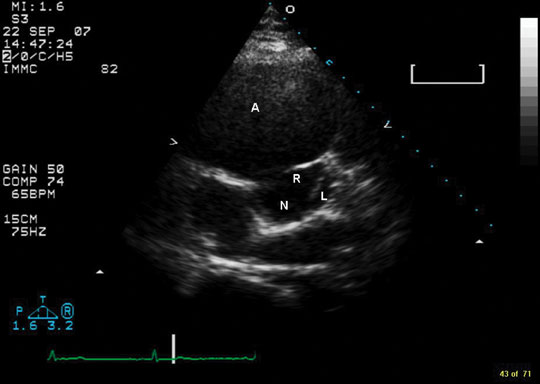

What are sinuses of Valsalva?

Definition. A sinus of Valsalva aneurysm (SOVA) is an enlargement of the aortic root area between the aortic valve annulus and the sinotubular ridge. 1. In a normal heart, the left and right sinus each contain their respective coronary artery ostia, whereas the posterior sinus is a noncoronary sinus.

What is the aortic sinus?

The aortic sinus, or bulb of the aorta (sinus of Valsalva), is a dilation of the aorta at its origin, from which the coronary arteries arise.

What is sinus of Valsalva?

A sinus of valsalva aneurysm (SOVA) is an abnormal dilatation of the aortic root located between the aortic valve annulus and the sinotubular junction. It occurs as a consequence of weakness of the elastic lamina at the junction of the aortic media and the annulus fibrosis. The function of the normal sinuses is to prevent occlusion of the coronary artery ostia during systole when the aortic valve opens. The normal sinus diameter is less than 4.0 cm for men and 3.6 cm for women. Sinus of Valsalva aneurysms can be either congenital or acquired. They are usually isolated, though rare case reports describe aneurysms involving two to three sinuses. Sinus of valsalva aneurysm rupture is a potentially fatal complication and should prompt an urgent referral to a cardiothoracic surgeon for consideration of repair. This activity describes the risk factors, evaluation, and management of sinus of valsalva aneurysms and highlights the role of the interprofessional team in enhancing care delivery for affected patients.